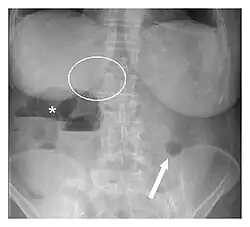

| Plain abdominal radiograph showing Rigler's triad (pneumobilia indicated by the circle, ectopic gallstone indicated by the arrow, and bowel distension indicated by the asterisk). | |

Rigler's triad is a combination of findings on an abdominal radiograph of people with gallstone ileus, a condition where a large gallstone causes bowel obstruction. Rigler's triad consists of: (1) small bowel obstruction, (2) a gallstone outside the gallbladder, and (3) air in the bile ducts.[1] It bears the name of Leo George Rigler (1896–1979), who described it in 1941.[2][3] It is not the same as Rigler's sign.

It is most commonly seen in 6th to 7th decade of life and affects females more often. Most patients with gallstone ileus are asymptomatic. Due to the fistula formation between the small intestine and gallbladder, large stones can lodge in the small bowel, leading to its obstruction. Pneumobilia means air in the biliary tract. It is due to the transfer of air from bowel through the fistula into the biliary tract.